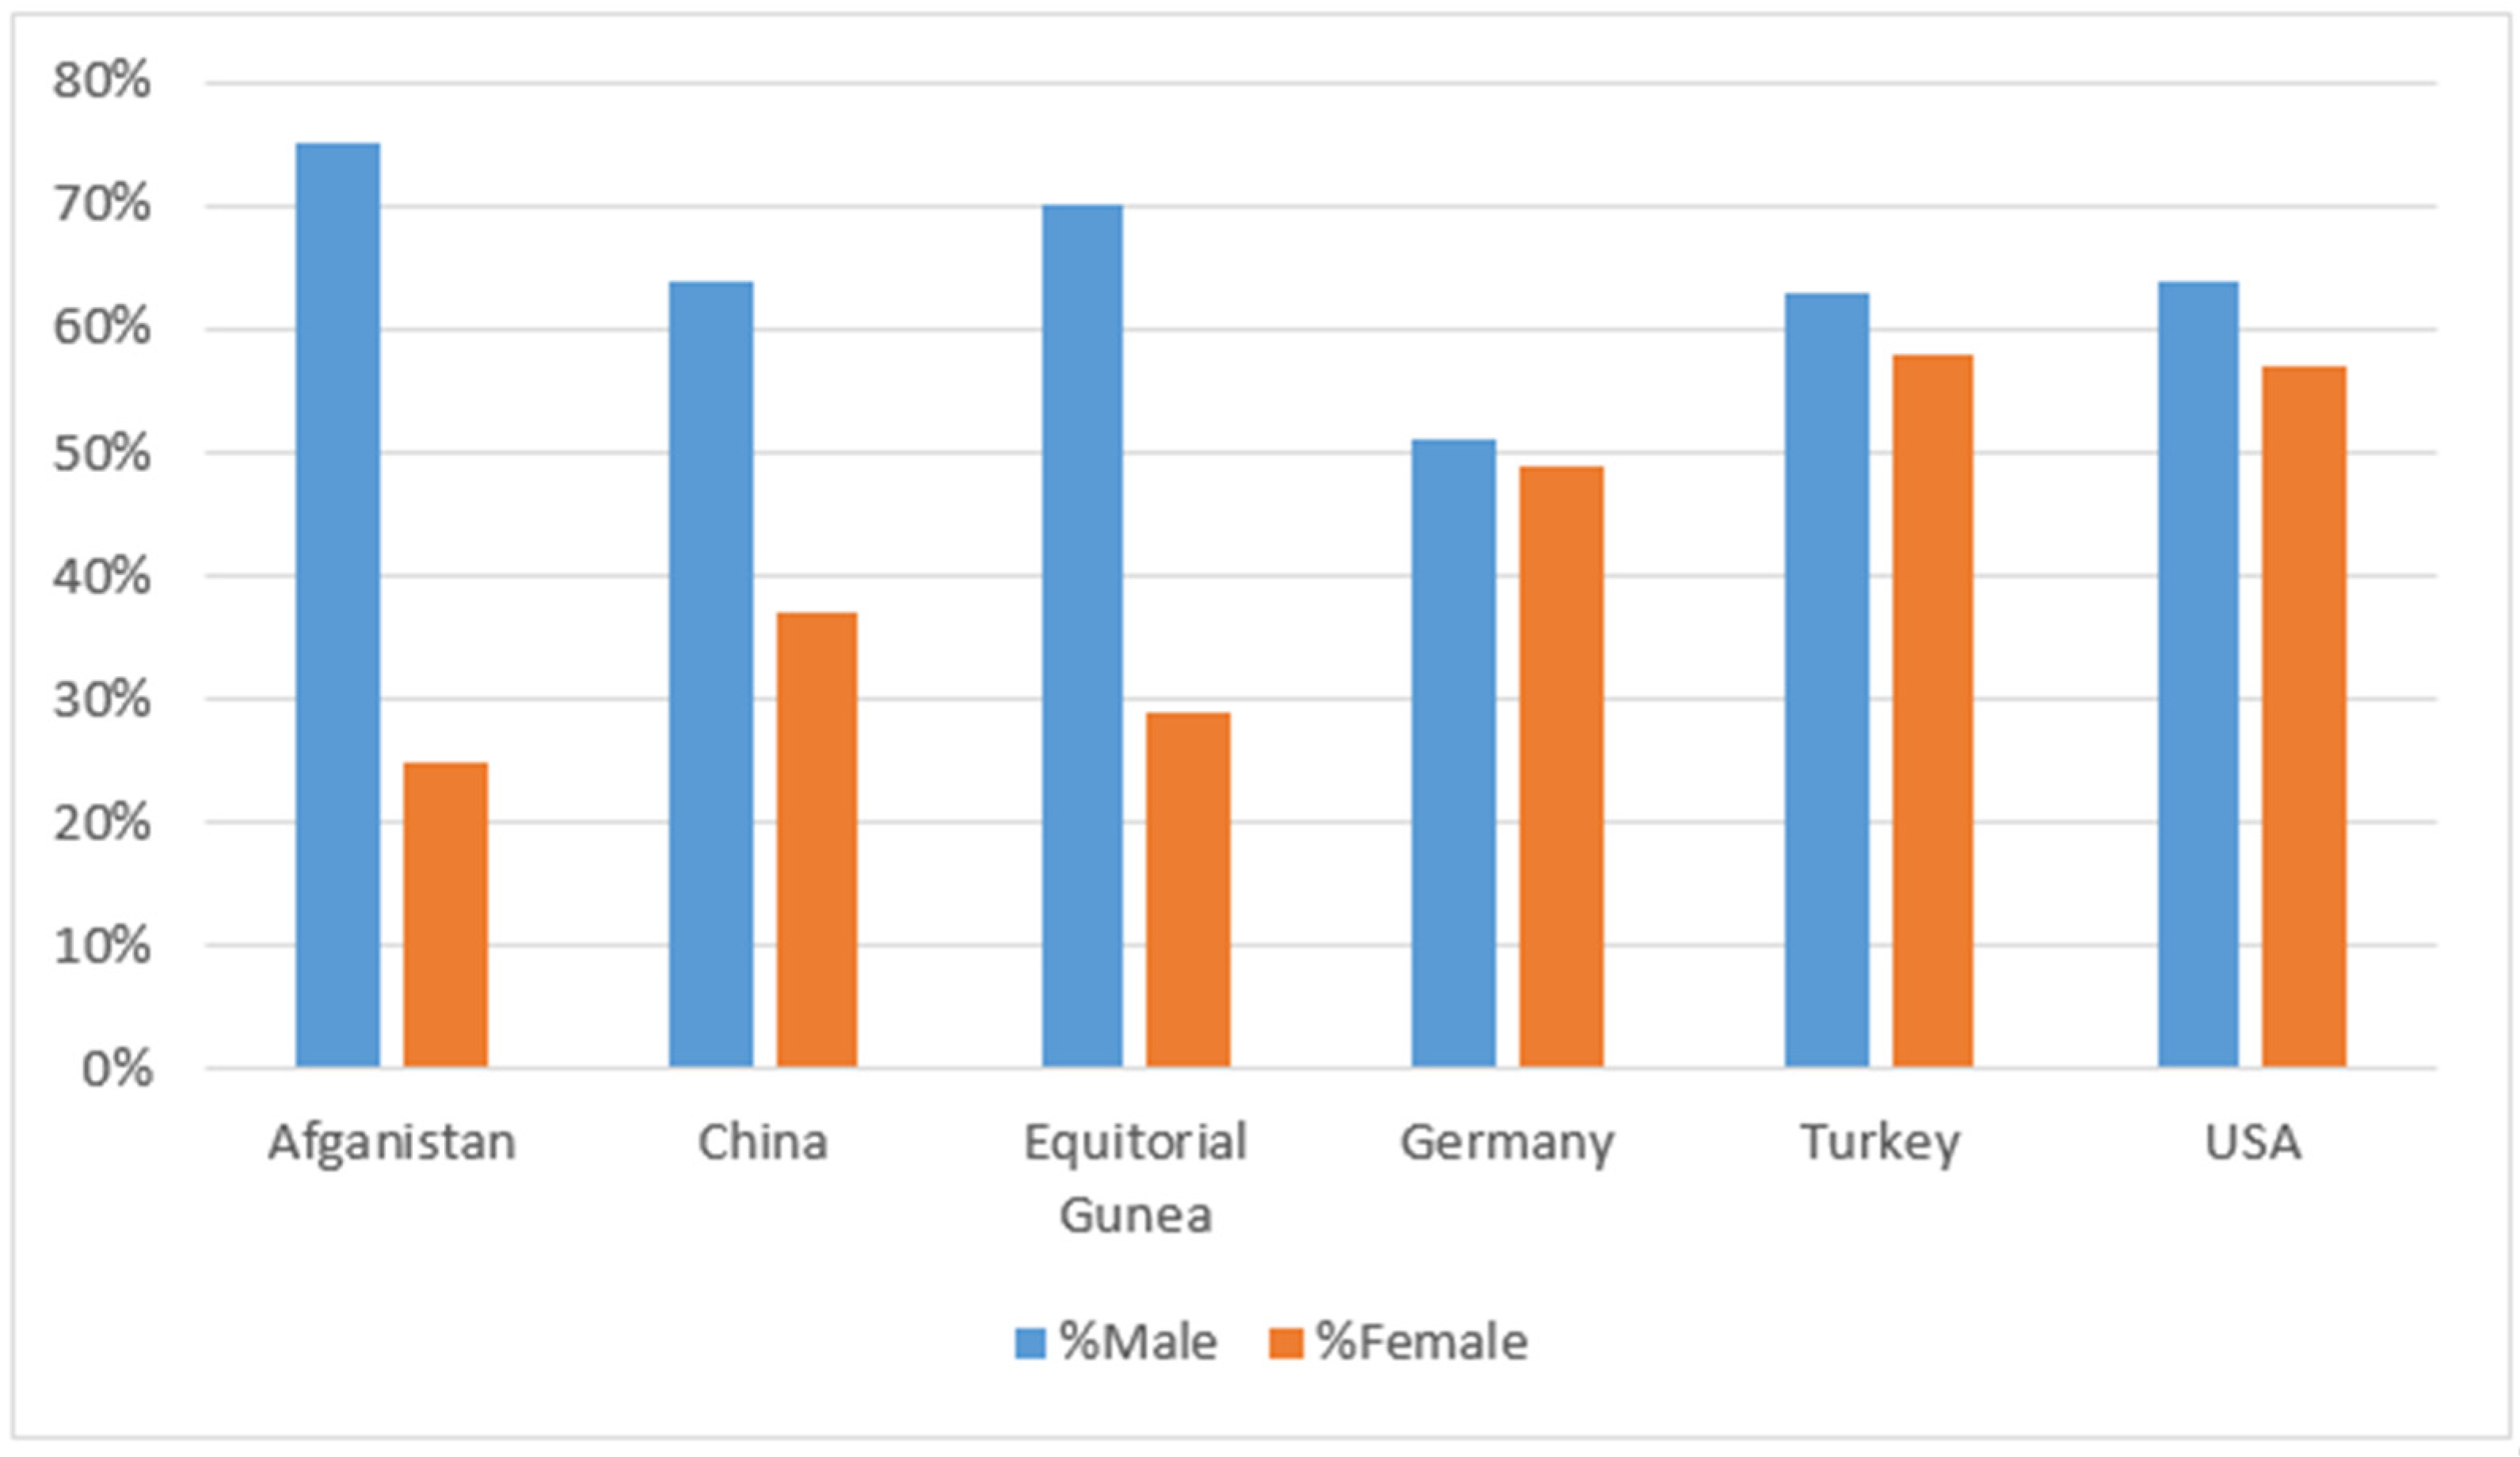

3. AI for COVID-19 Diagnosis

4. Result: COVID-19 Status